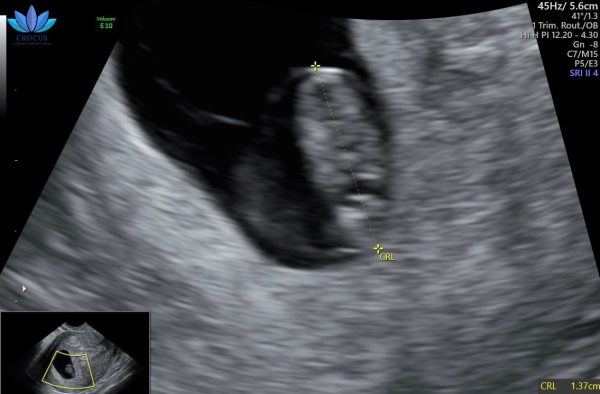

Idag går Ida in i vecka 9, igår hade hon ytterligare ett ultraljud där vi fick se det lilla hjärtat slå ❤️